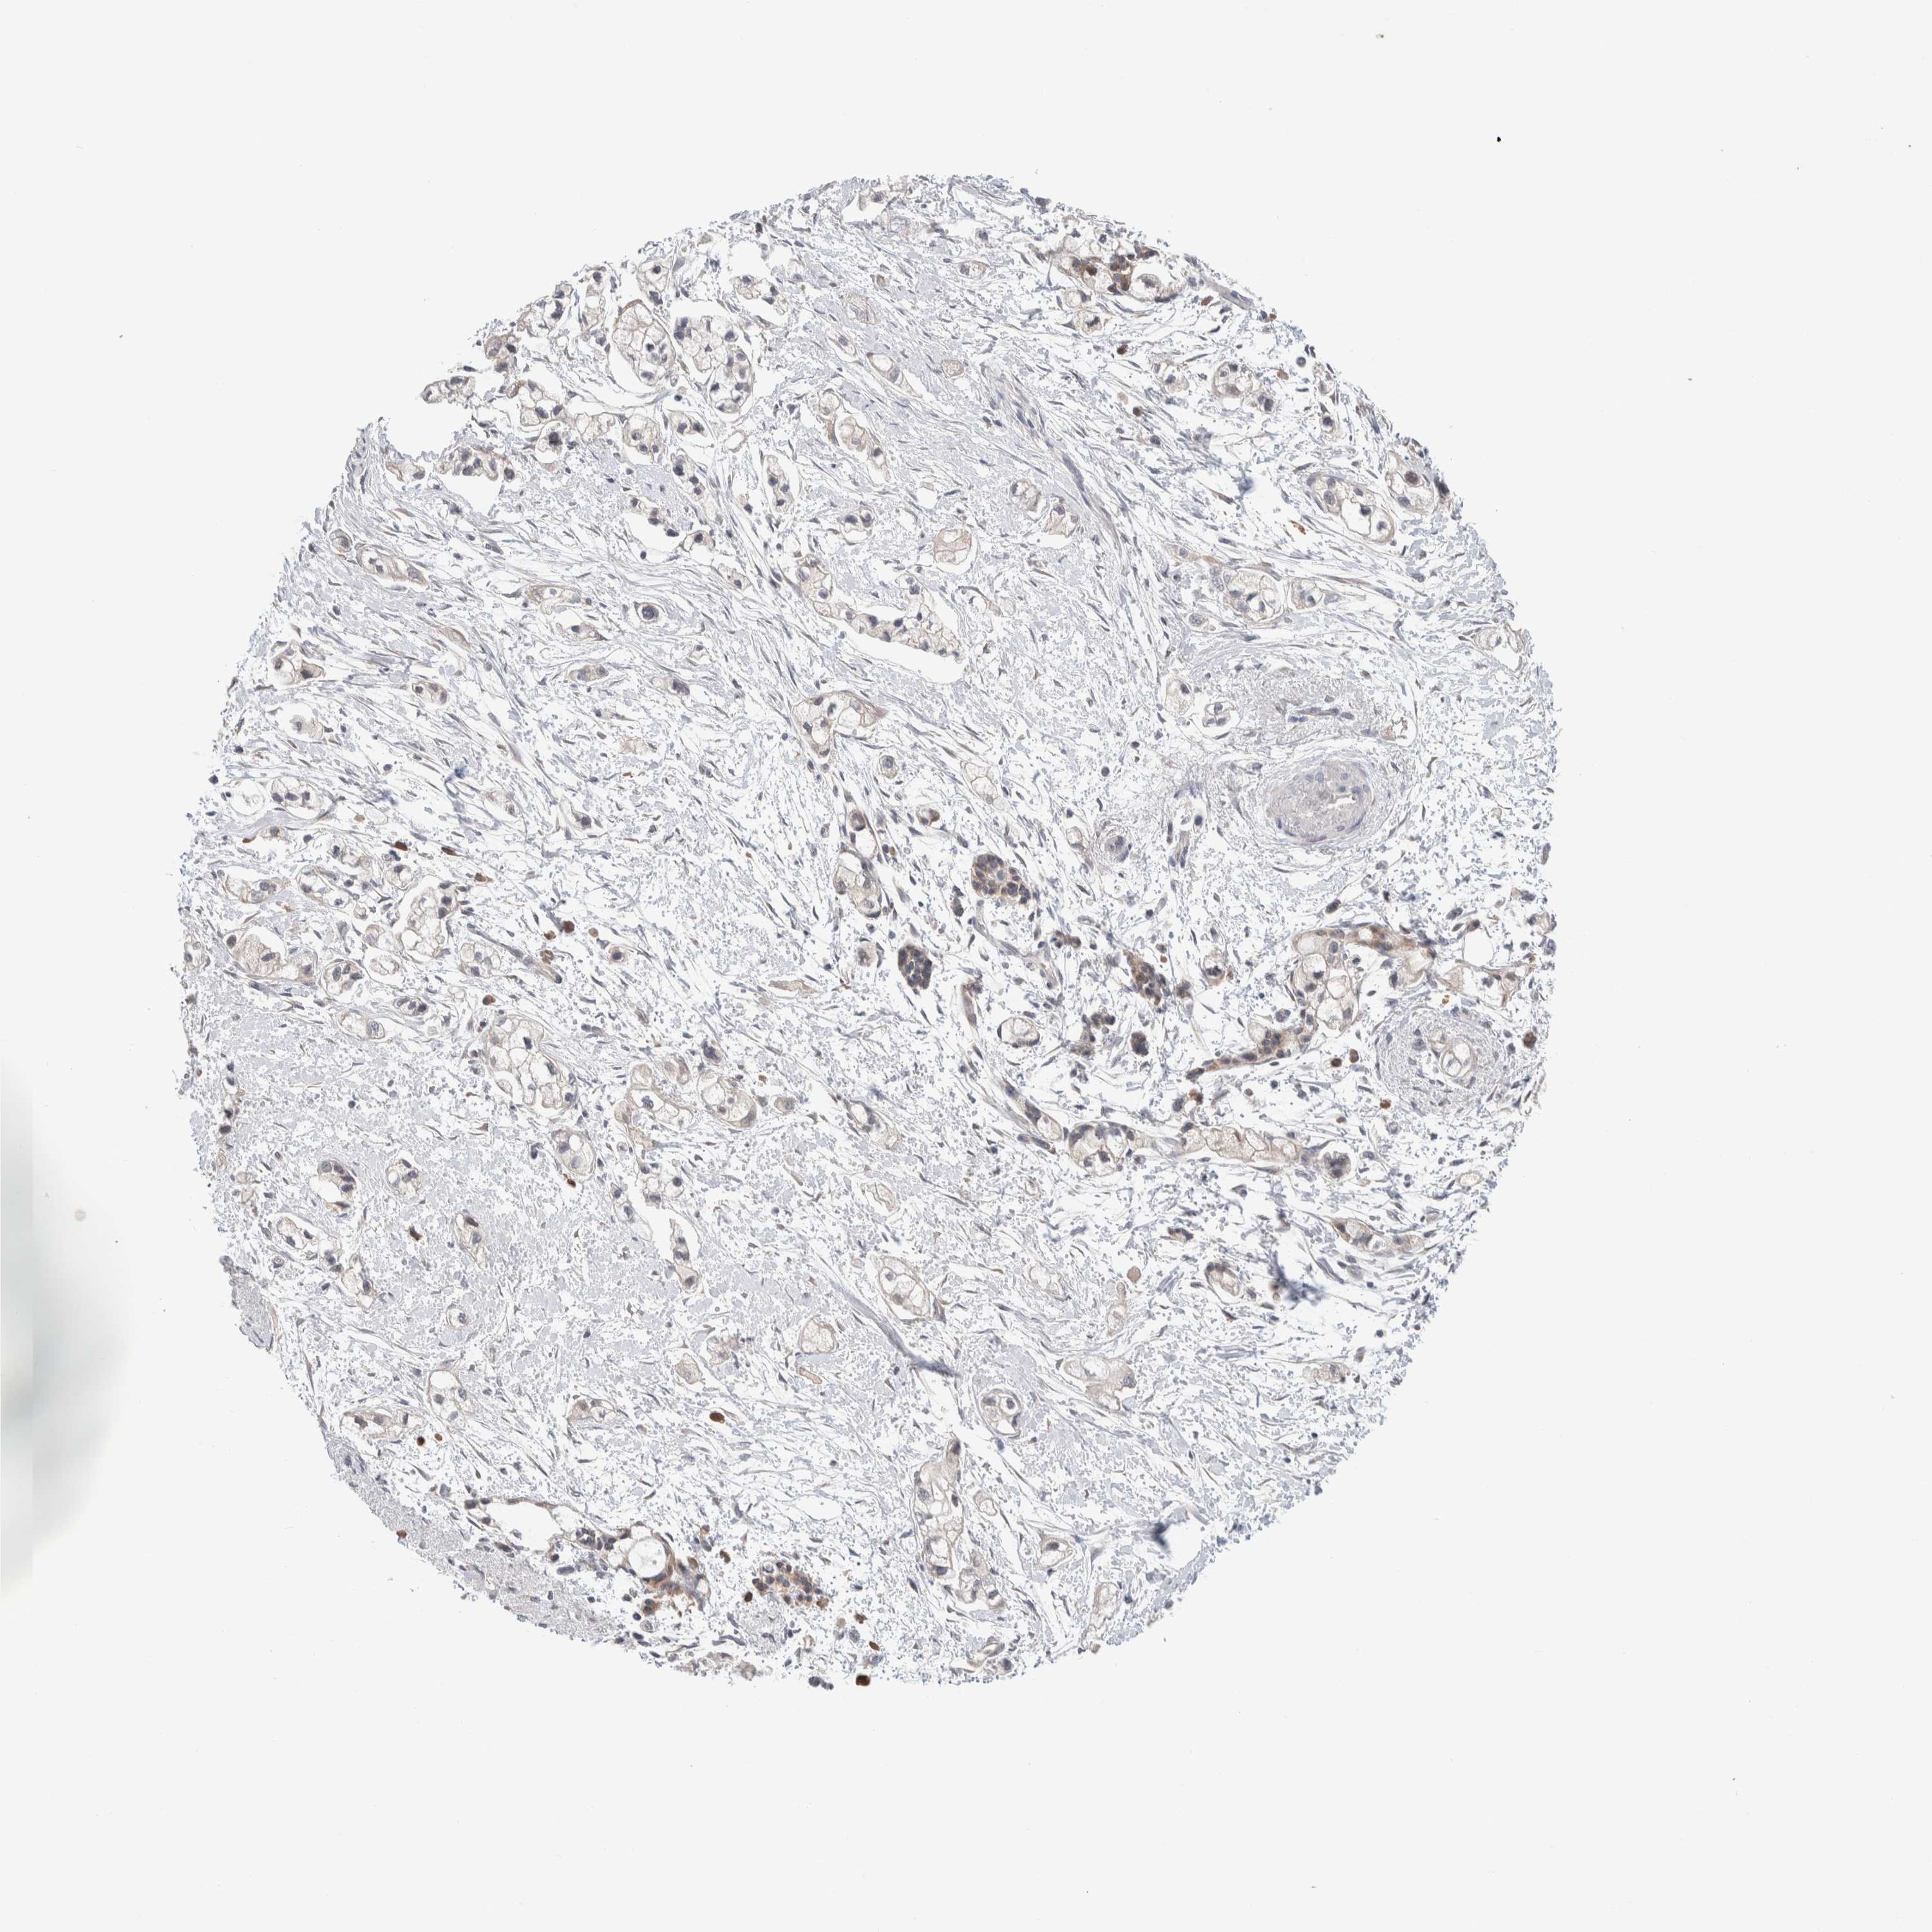

PANCREATIC CANCER - Protein expressioni

A mouse-over function shows sample information and annotation data. Click on an image to view it in a full screen mode. Samples can be filtered based on level of antibody staining by selecting one or several of the following categories: high, medium, low and not detected. The assay and annotation is described here.

Note that samples used for immunohistochemistry by the Human Protein Atlas do not correspond to samples in the TCGA dataset.

Antibody stainingi

Antibody staining in the annotated cell types in the current human tissue is reported as not detected, low, medium, or high, based on conventional immunohistochemistry profiling in selected tissues. This score is based on the combination of the staining intensity and fraction of stained cells.

Each image is clickable and will lead to virtual microscopy that enables deeper exploration of all samples and also displays staining intensity scores, fraction scores and subcellular localization as well as patient and tissue information for each sample.

Antibody HPA024406

Staining

High

Medium

Low

Not detected

Intensity

Strong

Moderate

Weak

Negative

Quantity

>75%

75%-25%

<25%

None

Location

Nuclear

Cytoplasmic/membranous

Cytoplasmic/membranous,nuclear

Adenocarcinoma, NOS